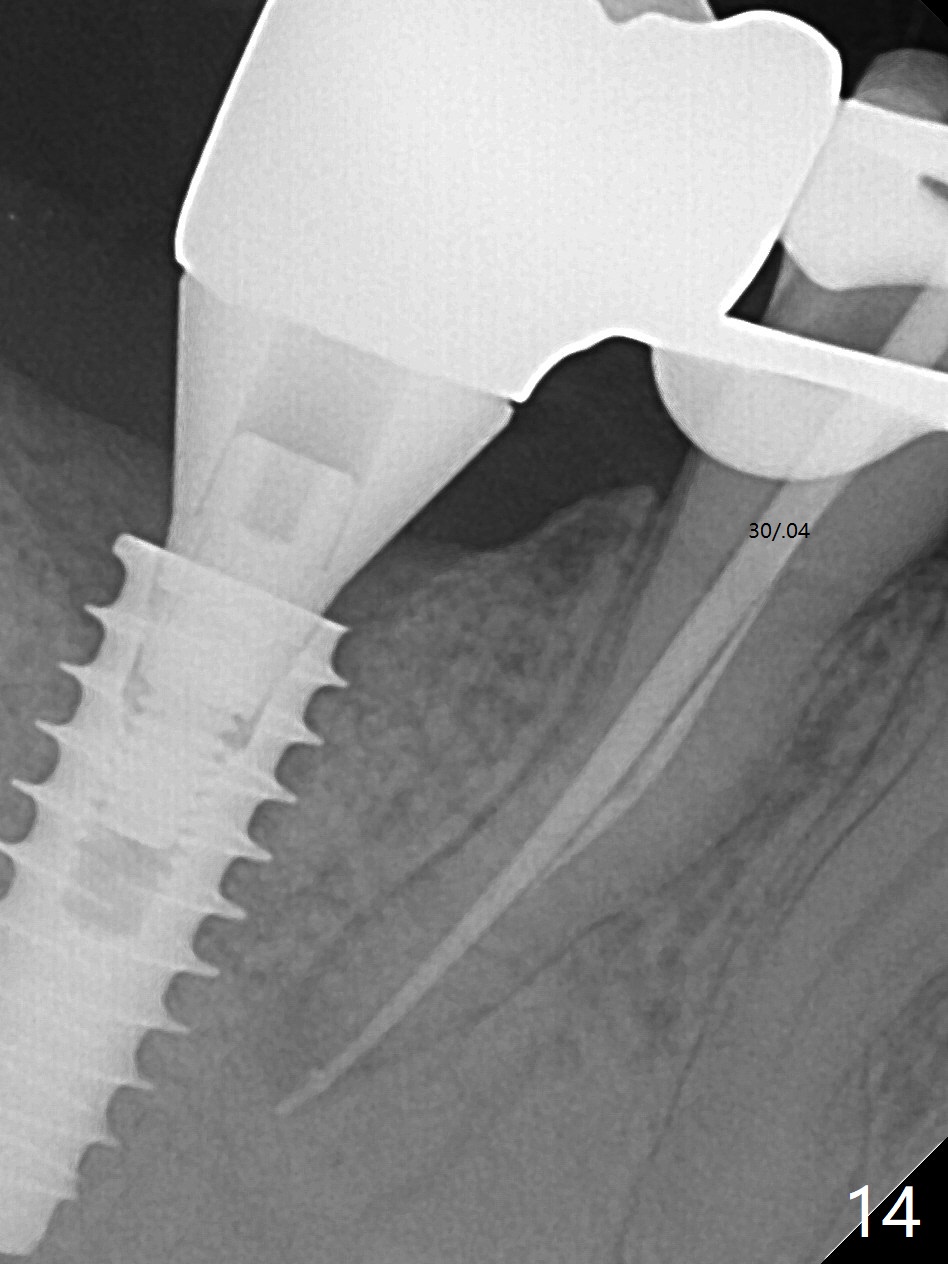

Bone graft seems to sink down and becomes denser 3 months postop (Fig.6 arrow). The bone continues being denser 5 months postop (Fig.7). There is periapical radiolucency of the tooth #29 (^). RCT is done (Fig.8). The pain persists 2 weeks postop (Fig.9,10). There is no missing canal (Fig.9). The apex is close to the implant (Fig.9 *). Apicoectomy will be performed if needed. It appears that the implant is also placed buccal (Fig.10 <) and/or the implant too large for the site. Therefore there should be a 2-3 mm buccal gap before and after implant placement. Separation and reflection of the buccal flap allows better visibility. The pain persists 1 month post RCT and 6 months post implant placement. RCT retreatment is initiated (Fig.11,12) with placement of Calcium Hydroxide paste after redebridement with 30/.04 rotary file at 23.5 mm (.5 mm longer than the earlier RCT, Fig.13). RCT retreatment finishes with apparent transportation and extrusion in 4 weeks (Fig.14,15), followed by apicoetomy (Fig.16,17) (20 days later)). Discomfort remains 2.5 months postop (Fig.18). Keep watching.